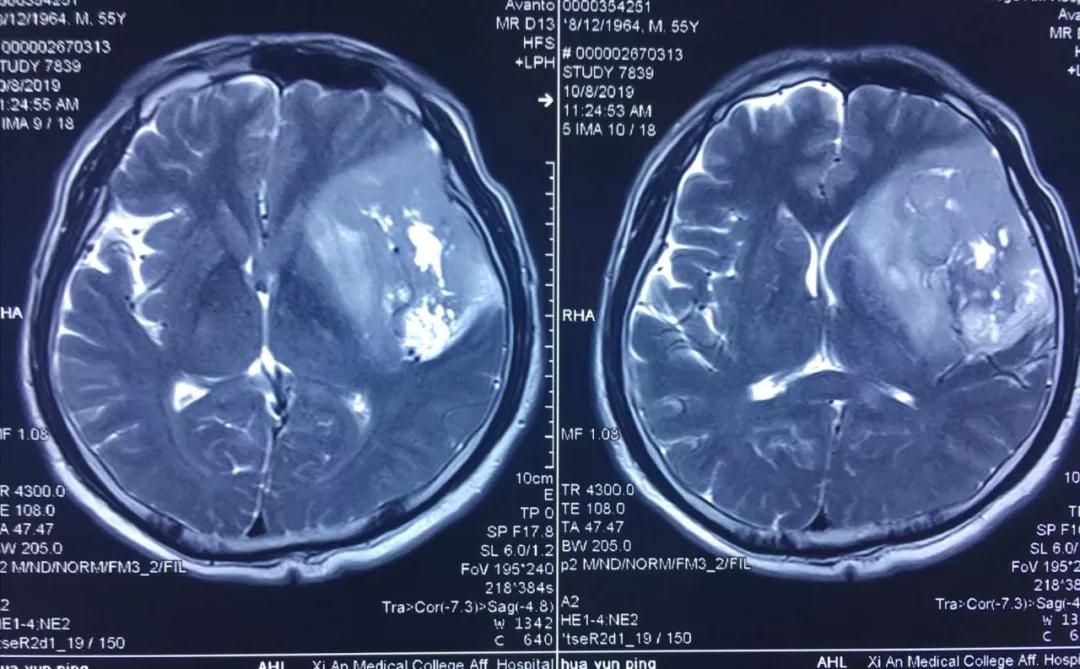

患者李某,今年55歲,因近年出現(xiàn)間歇性面部抽搐,一直未給予重視,近來發(fā)作頻繁,經(jīng)朋友建議在外院行頭顱核磁檢查,發(fā)現(xiàn)顱內(nèi)巨大占位性病變,病變位于左側(cè)額、顳和深部腦島葉,達(dá)8.5?5.5?3cm,且侵犯語言功能區(qū),顱內(nèi)占位效應(yīng)明顯,中線偏移1cm,且腫瘤已經(jīng)瀕臨腦疝邊緣,如不及時(shí)進(jìn)行手術(shù)干預(yù),隨時(shí)有腦疝可能,危及患者生命。

經(jīng)多方了解后,在朋友的推薦下,患者慕名來到西安國際醫(yī)學(xué)中心找到了腦科醫(yī)院高國棟院長(zhǎng),高院長(zhǎng)帶領(lǐng)以賀世明主任為首的神經(jīng)外科團(tuán)隊(duì),對(duì)患者的病情及治療方案等進(jìn)行討論,憑借多年的臨床經(jīng)驗(yàn),結(jié)合患者影像結(jié)果判斷為顱內(nèi)膠質(zhì)瘤,并建議盡快實(shí)施手術(shù)切除。